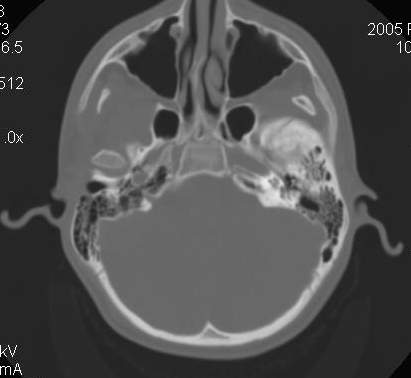

Пациент В., 13 лет. Диагноз: Костный анкилоз левого височно-нижнечелюстного сустава (ВНЧС), левосторонняя микрогения. Болеет с 2-х летнего возраста. Возможная причина развития анкилоза – воспалительный процесс (в первые 1,5 года жизни часто болел простудными заболеваниями, травму родители отрицают). В 3 и 5 лет проводилась редрессация – безуспешно.Прилагаются: ортопантомограмма, кадры СКТ с 3Д реконструкцией. Вопросы: определение тактики лечения – вид и сроки реконструктивно-пластической операции (этапов операции), а именно – неоартропластики и устранения микрогении, медикаментозная терапия в до- и послеоперационный период, ортодонтическое лечение.